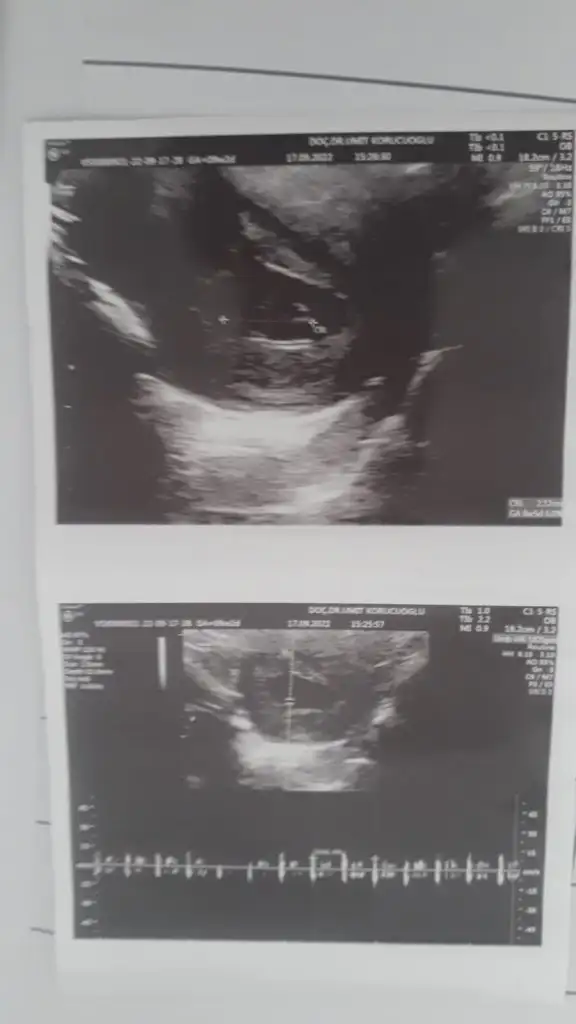

merhaba 8+4 ultrason goruntum tahmın alabılırmıyım :)

• WhatsApp Image 2022-09-24 at 10.46.25.webp

13,3 KB · Görüntüleme: 65